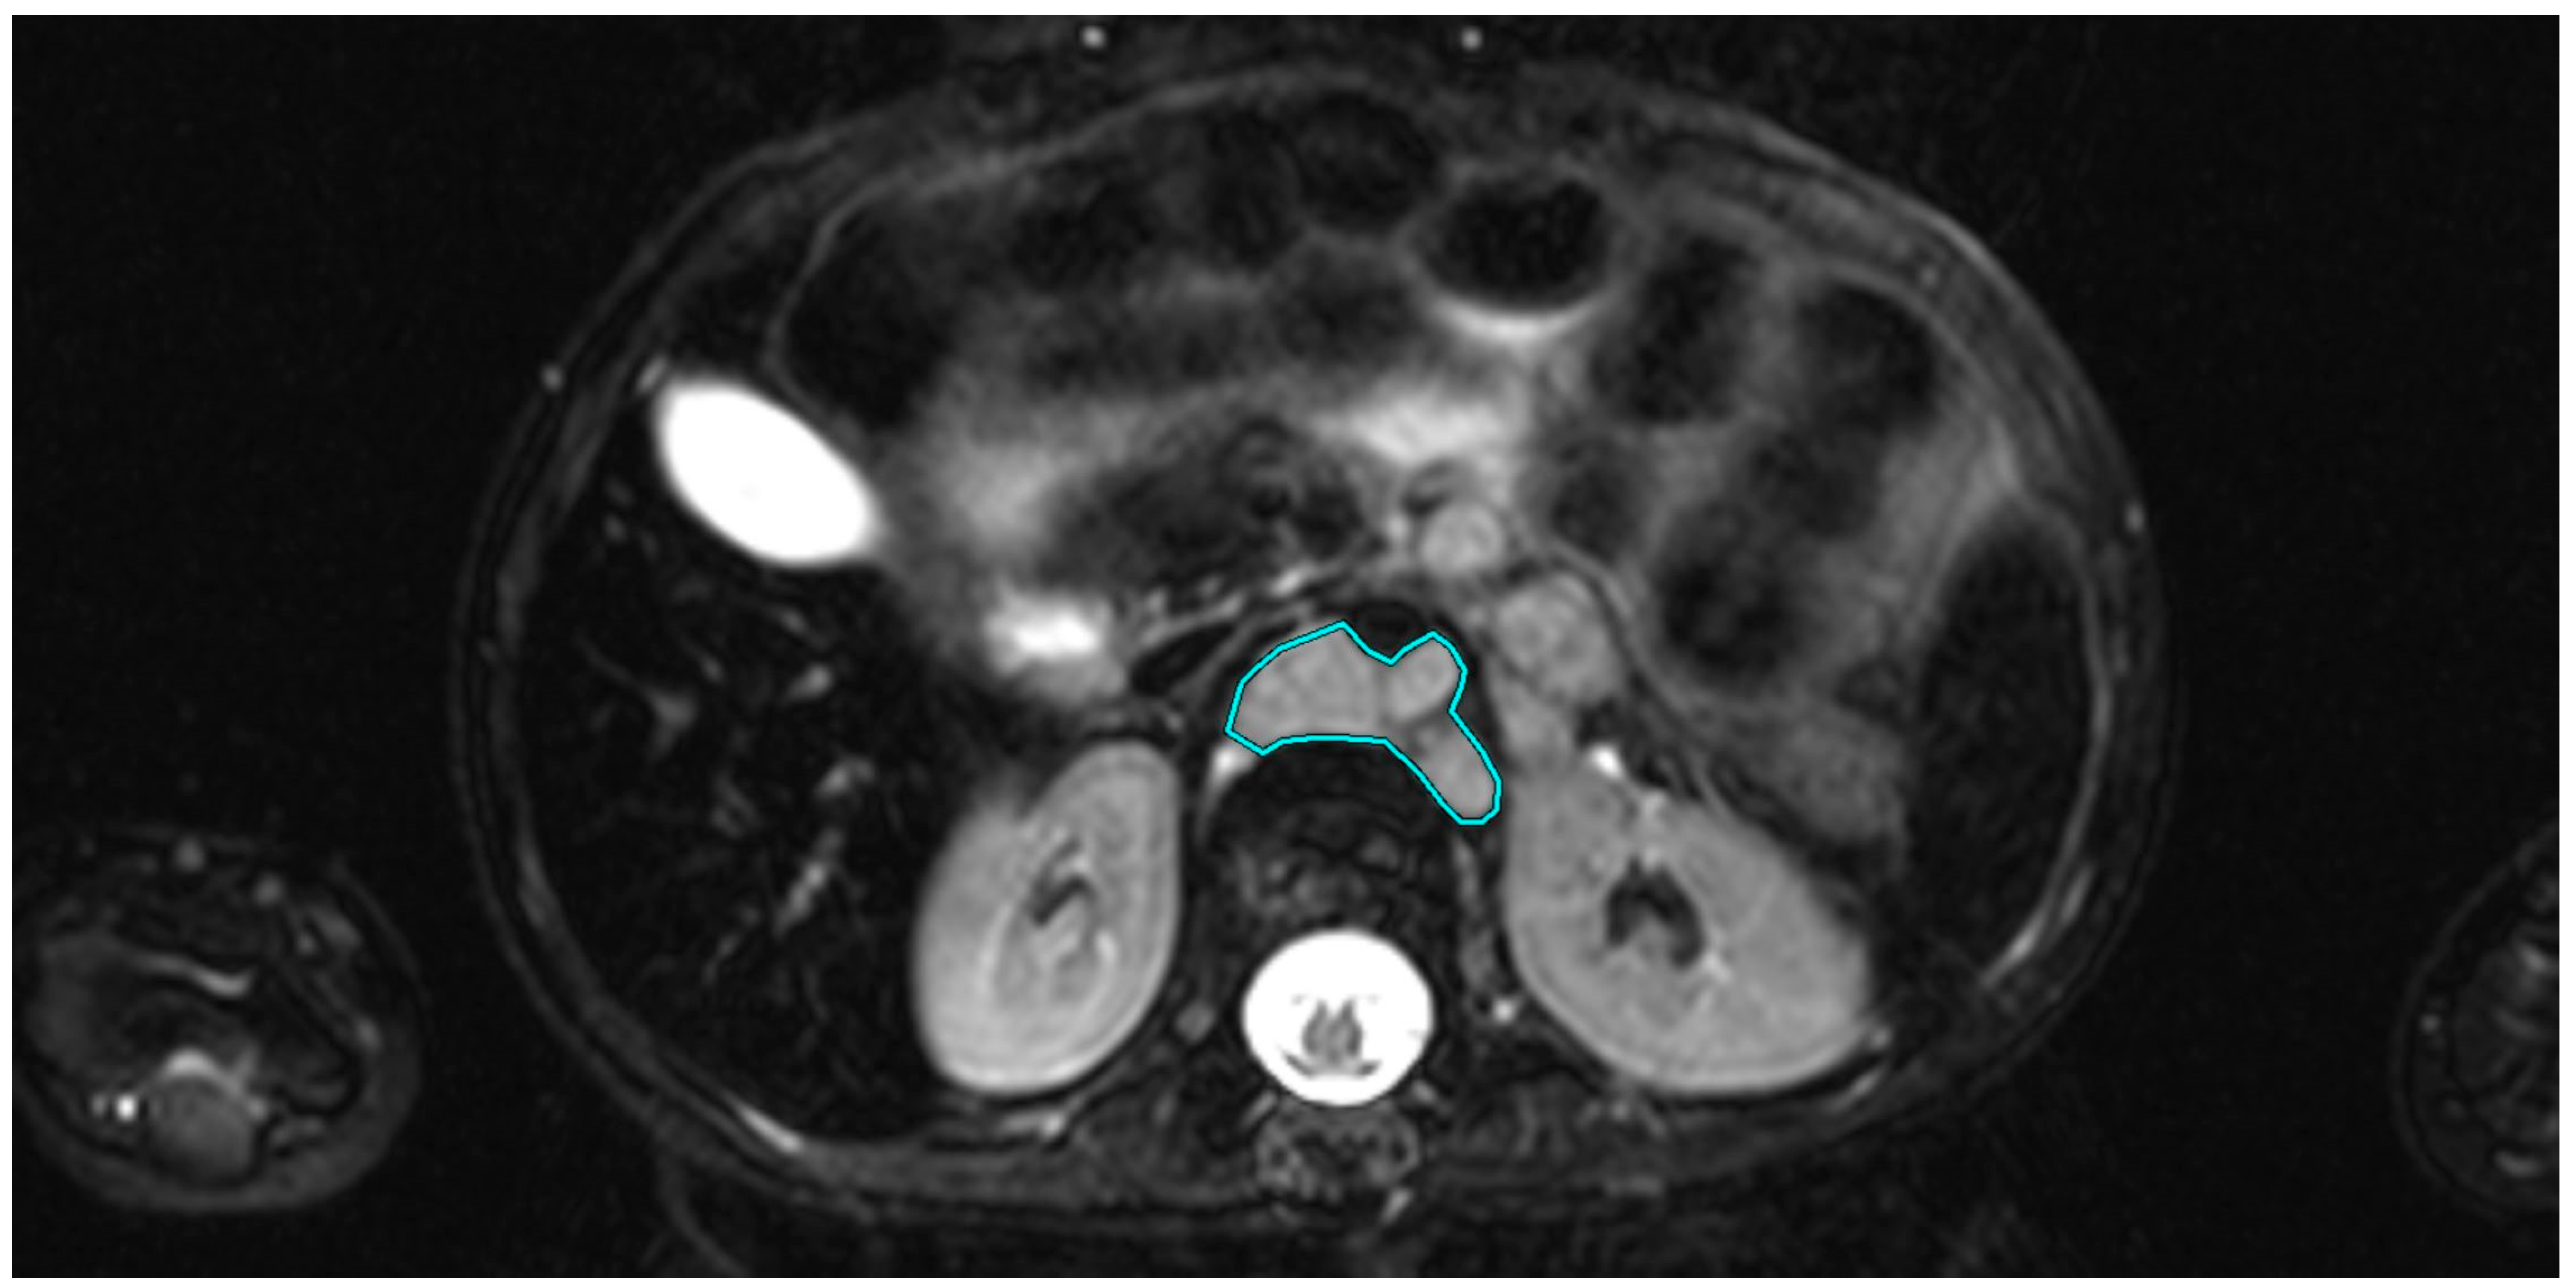

In addition, the tumor volume was determined for each observed tumor manifestation. For this purpose, in the axial sequence with the best visibility of the respective tumor manifestation, the tumor was manually drawn with the “closed polygon” drawing tool in OsiriX (see Figure 1), and then the “compute volume” function was used to calculate the volume semi-automatically.

Figure 1. Axial T1-weighted image of a 2-year-old patient with stage IV neuroblastoma. The tumor is located para-aortally. The region of interest (ROI) is shown in turquoise, drawn using the “closed polygon” tool.